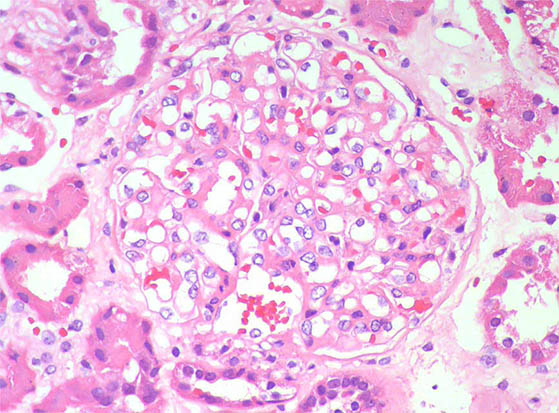

Figure 2. H&E, X400.

Figure 3. H&E, X400.